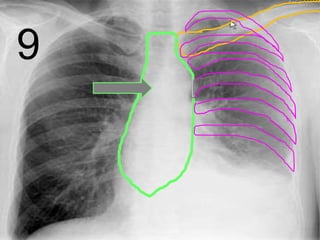

• Your skeletal system surrounds your most

important internal organs with a rib cage.

Sternum